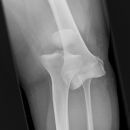

Knöcherner Ausriss Patellarsehne